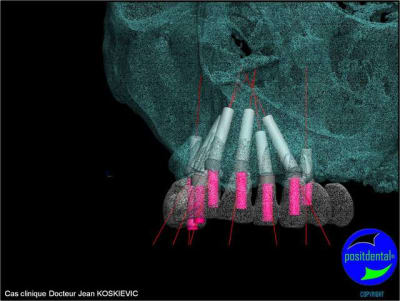

et la projet 10 implants maxillaire sup

10 en haut

donc ce sera minimum 8 en fonction du scan